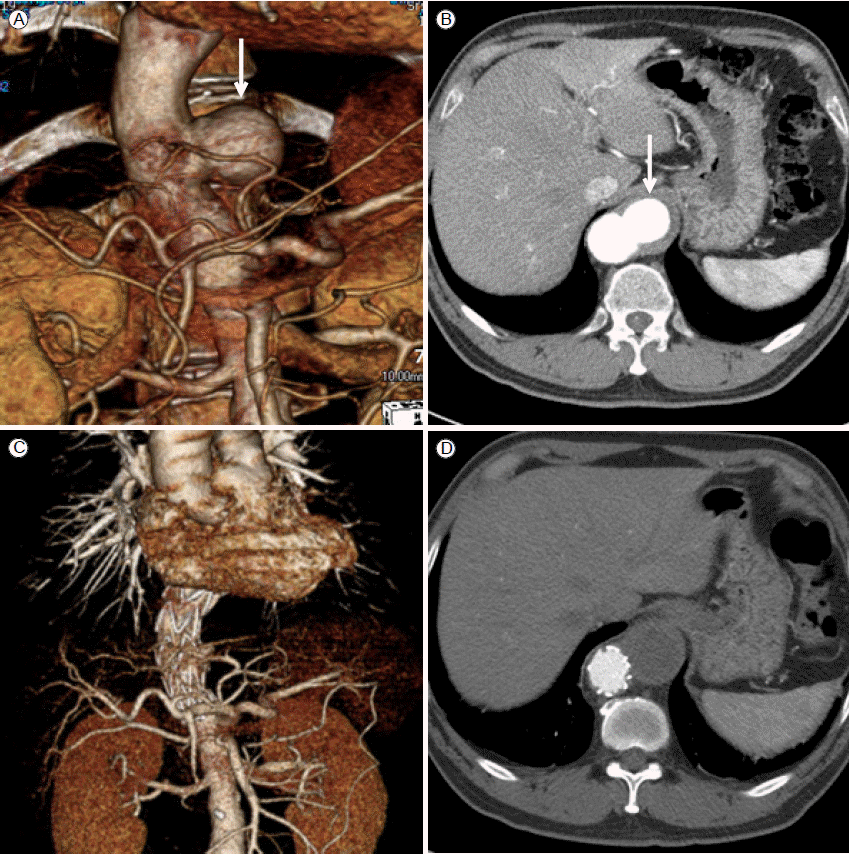

흉부대동맥확장증은 가장 흔한 흉부대동맥 중재적 치료의 적응증으로, 파열의 위험성이 수술로 인한 위험성보다 큰 경우 치료의 적응증이 된다. 대부분의 흉부대동맥확장증은 증상이 동반되지 않기 때문에 시술을 결정할 때는 환자의 동반된 질환이나 삶의 질을 고려하여 결정하여야 한다. 증상이 없는 경우 일반적인 중재적 치료의 적응증은 직경이 6 cm 이상인 경우이다. 통증이 동반된 경우는 파열에 임박하거나 파열로 진행되는 것을 의미하기 때문에 크기에 관계없이 중재적 치료의 적응증이 된다. 크기가 6 cm 이하인 경우에는 정기적으로 추적 관찰하면서 크기가 6 cm 이상이 되거나 1년에 1 cm 이상 커지는 경우 파열의 위험성이 높으므로 시술의 적응증이 된다(Fig. 1) [1,4].

경우에 따라서 근위부 봉인부위의 길이가 충분하지 않을 경우 좌쇄골하동맥을 넘어서 스텐트 그라프트를 시술할 수도 있는데 이때 주요 분지혈관의 우회술이 필요할 수도 있다(Fig. 2). Ishimaru [10]는 근위부 봉인부위의 위치에 따라 5개의 구역으로 나눠 구분하였다(Fig. 2A).

만약 zone 0/1에 스텐트 그라프트를 시술한다면 시술 전 완두동맥이나 좌총경동맥을 좀 더 근위부 쪽으로 우회술하여 근위부 봉인부위를 충분히 확보한 후 스텐트 그라프트를 시술하게 된다(Fig. 3). 우회술 없이 좌쇄골하동맥을 막는 것에 대해서는 아직 논란이 여지가 있는데 일반적으로 시술 전 두경부 혈관들을 충분히 검사한 후 재관류 여부를 결정하게 된다. 수술적 방법은 다양하다.